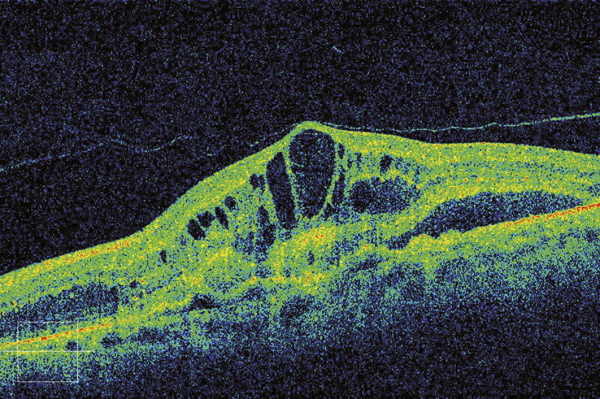

© Jean-François Korobelnik, La Revue du Praticien Tomographie en cohérence optique : vaste lésion avec épaississement rétinien, œdème intrarétinien, et décollement rétinien localisé.